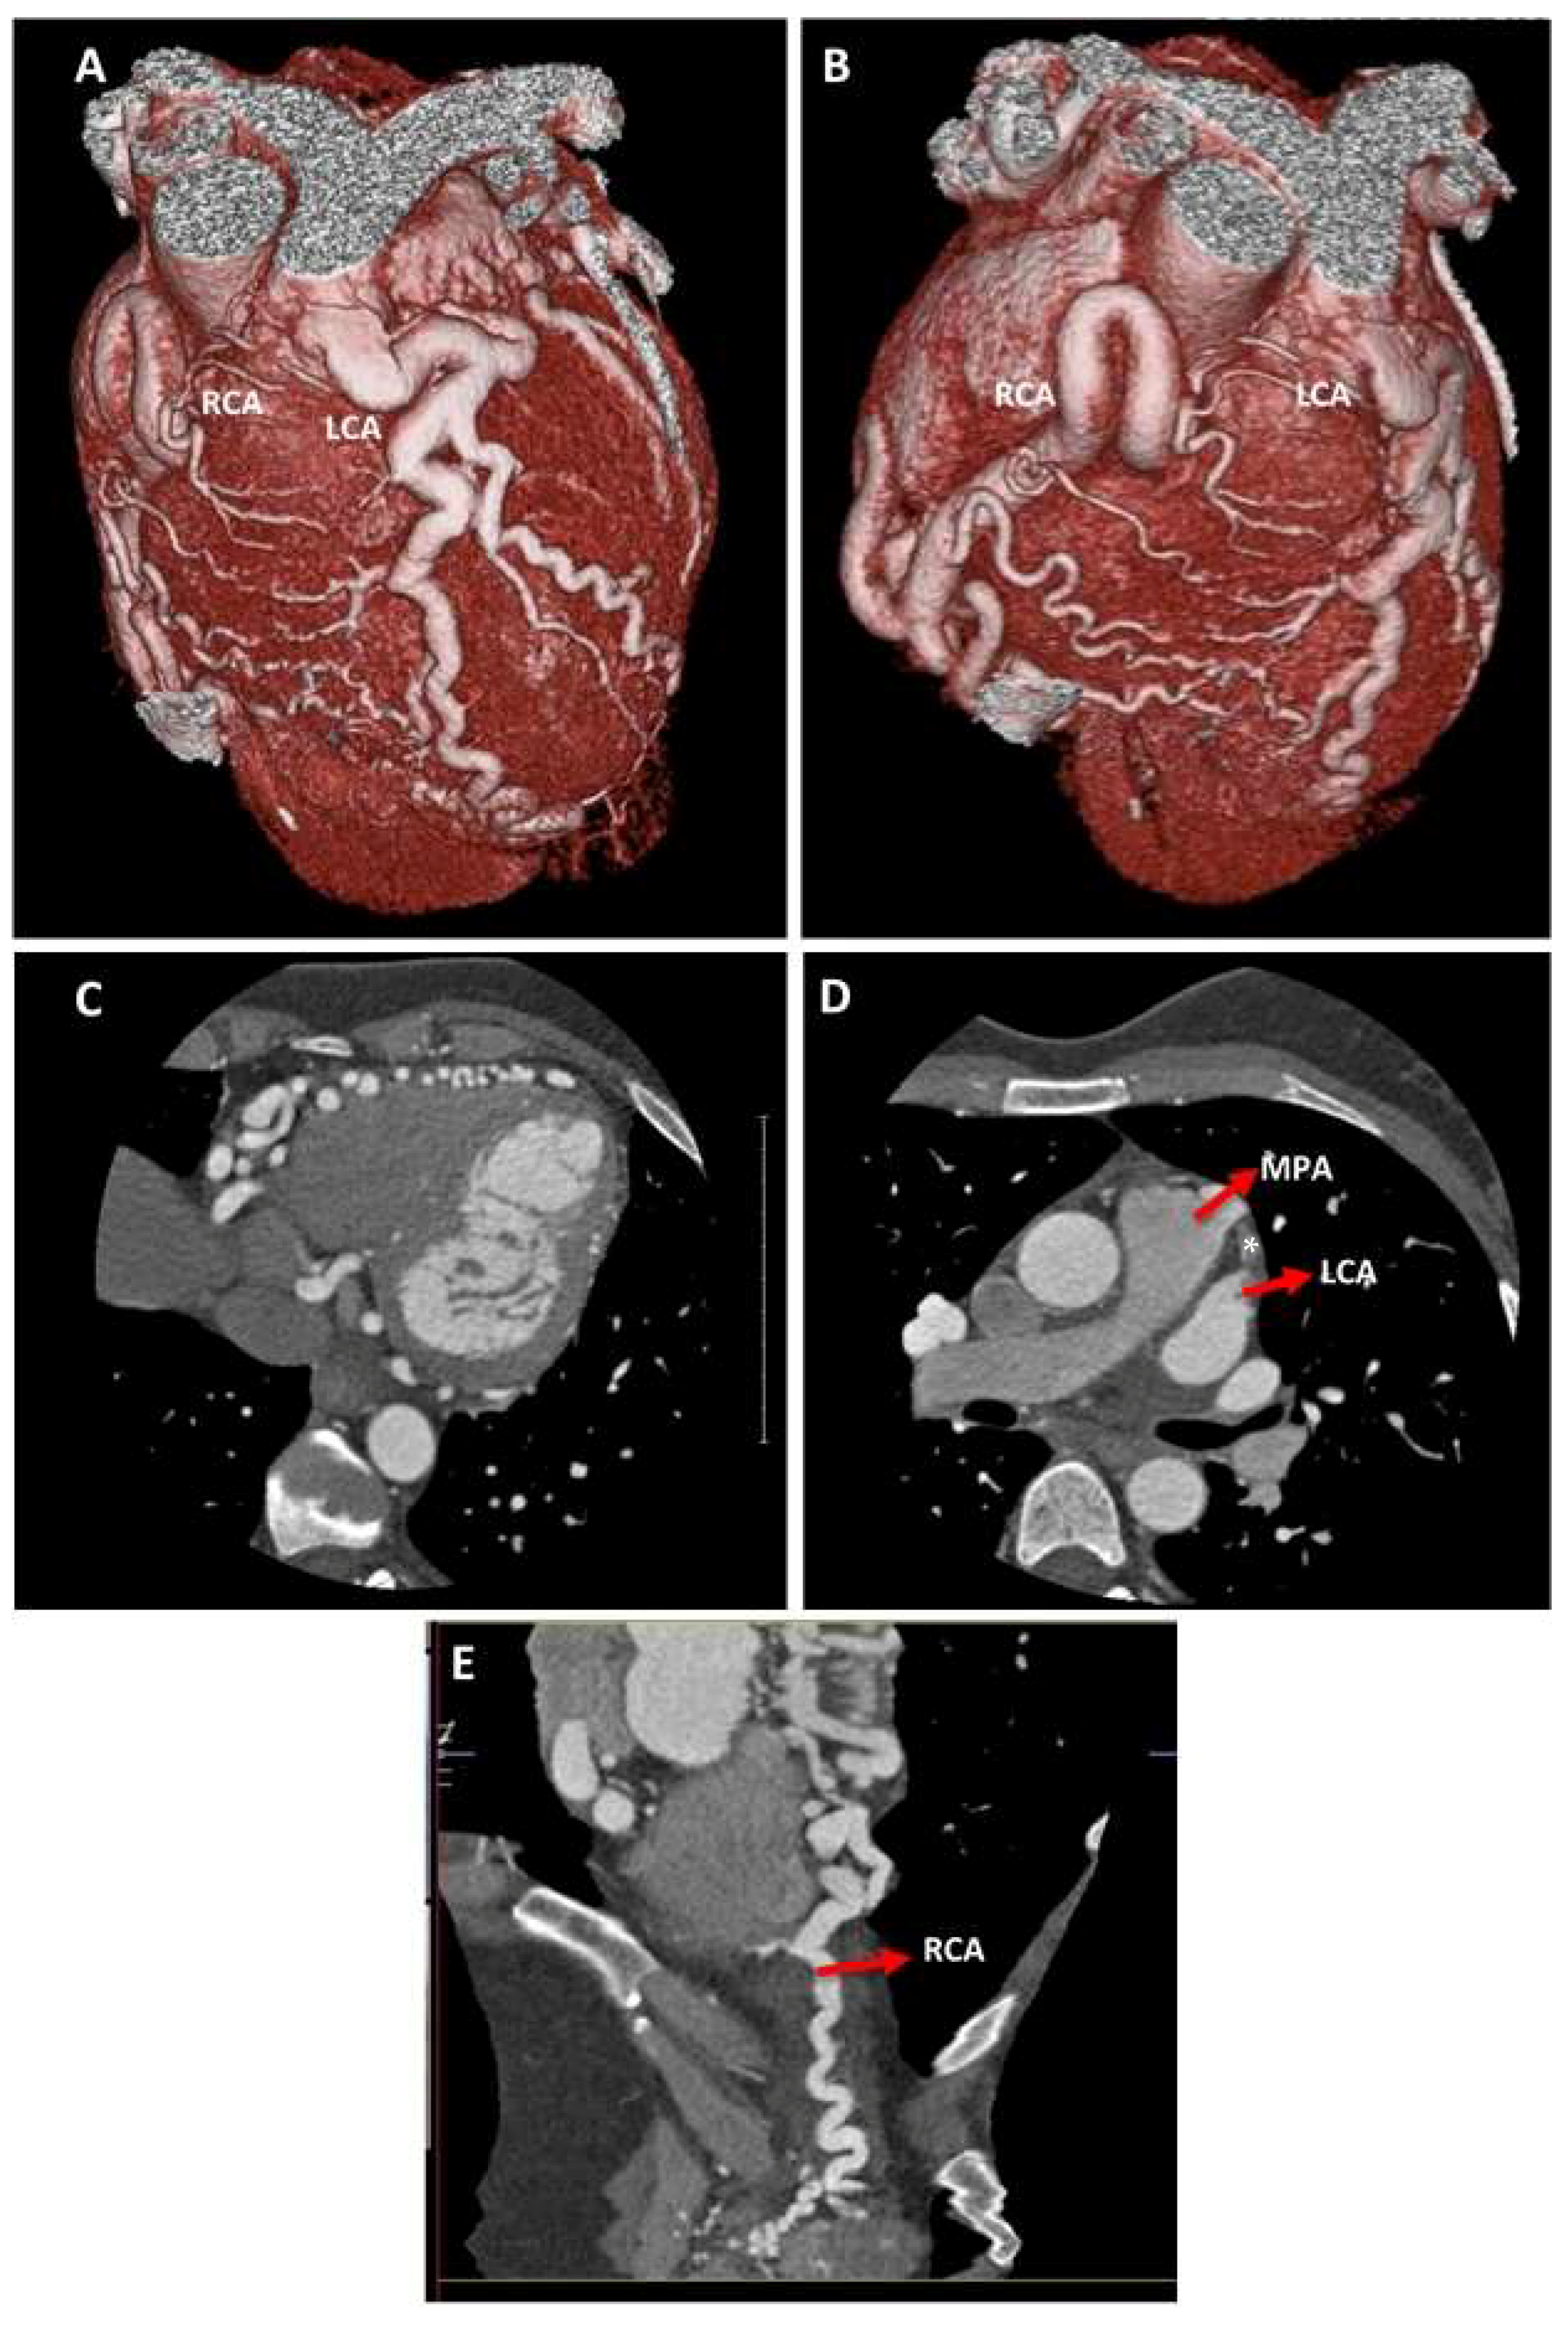

In order to delineate the origin of the left coronary artery, a Computer Tomography Coronary Angiogram (CTCA) was later performed and illustrated that both arteries were diffusely aneurysmal. Whilst the right coronary artery originated from the right coronary sinus, the left coronary artery anomalously originated from the left anterior pulmonary sinus of the main pulmonary artery (Figure 5). Furthermore, there was a right dominant coronary artery system with multiple collateral vessels (also visualised on the coronary angiogram) and no evidence of coronary artery stenosis. This suggested a diagnosis of ALCAPA.

Figure 5.

Computer tomography coronary angiogram (CTCA) with contrast. Heart rate control and coronary vasodilatation was achieved using an oral beta-blocker and sublingual glyceryl trinitrate spray, respectively. The right coronary artery (RCA) appears diffusely dilated and has a normal origin from the right coronary sinus. The left coronary artery (LCA) has an anomalous origin from the main pulmonary artery (MPA). There is a right dominant coronary artery system, where multiple collaterals arise from the RCA, spanning towards the LCA. The left main stem (LMS) is also dilated and divides into the left anterior descending artery (LAD) and the left circumflex artery (LCx). Both RCA and LCA, with the collaterals, appear tortuous. There is no evidence of coronary artery calcification. In summary, CTCA with contrast confirms that there is an anomalous origin of the left coronary artery from the main pulmonary artery (ALCAPA). (A,B) Volume rendering demonstrating anomalous origin of the LCA from the MPA and marked dilatation and tortuosity of the coronary arteries. Collaterals between RCA and LCA are also seen. (C) Axial view demonstrating the marked tortuosity of the RCA. (D) Axial view of the origin of LCA from MPA (*). (E) Multiplanar reconstruction demonstrating a dilated and tortuous RCA.